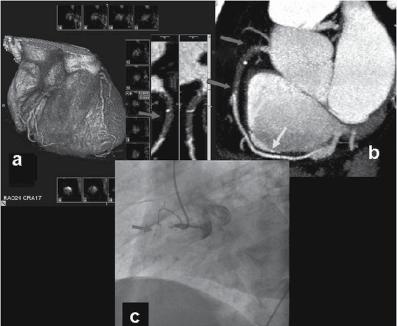

Figure 1.1 (A) Normal case: coronary angiography (left) and three‐dimensional CTA (right) showing normal left anterior descending (LAD, arrow) and left circumflex (LCX) coronary arteries. The latter is partially covered by the left appendix in CTA. (B) Normal case: coronary angiography (left) and CTA (right) showing a normal dominant right coronary artery (RCA). (C) An 85‐year‐old man with atypical chest pain: (a) Maximal intensity projection (MIP) of CTA with tight mid‐LAD stenosis that correlates perfectly with coronary angiography (b). (D) Similar case as (C) but with the stenosis in the proximal RCA. (a–d) CTA and (e) coronary angiography. (E) A patient with tight stenosis in the LCX before a bifurcation. (a) and (b) CTA and (c) coronary angiography. (F) These images show that CTA may also demonstrate the presence of stenosis in distal vessel branches, in this case in the posterior descending branch of the RCA. (a–b) CTA and (c) coronary angiography. (G) These images show that CTA (a, b) may delineate the length of a total occlusion and visualize the distal branches (see arrows in (b)). Collateral flow from the LAD to the RCA may be better visualized with CTA than with conventional coronary angiography (c: here only the RCA is shown). (H) A 42‐year‐old patient with a stent implanted in the LAD six months before. The patient complained of atypical chest pain and underwent CTA. The MIP images of CTA (a–c) show no significant restenosis, but some plaque formation in the left main trunk (d, circle) that was not well seen in coronary angiography (e). The degree of luminal obstruction by the plaque can be exactly measured by intravascular ultrasound (IVUS) (f). The ECG showed mildly inverted T waves in V1–V3 during follow‐up (see Plate 1 in color plates).

intervention (PCI) (Figure 1.1). CTA may provide additional diagnostic information for clinical decision‐making in contemporary stable chest pain patients with intermediate pre‐test probability for IHD (Hoffmann et al. 2017). In additional to narrowing, CTA can provide information on coronary distribution, including abnormalities in the origin and course of the arteries, and presence of coronary aneurysms. However, the accuracy of assessing the severity of coronary stenosis in highly calcified lesions and within stents is reduced.